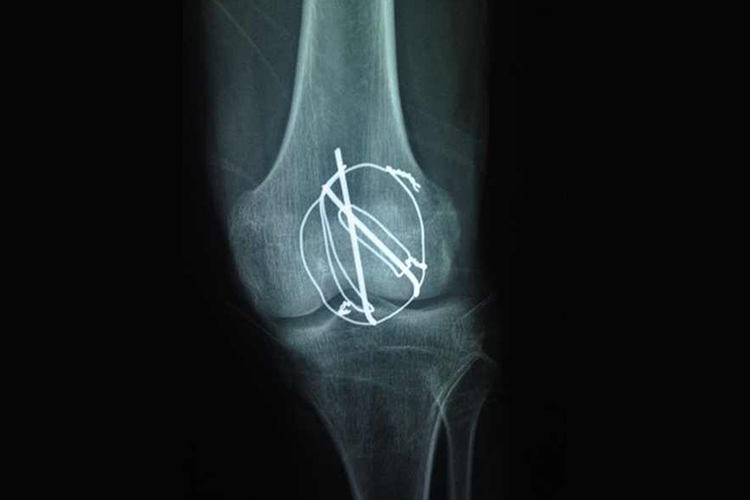

髌骨骨折

髌骨骨折一般采取张力带钢丝内固定术,医生自远折端骨折面,逆行穿出用两根直径1.5mm的克氏针(钢钉)固定骨折端,手伸入关节腔内,触髌骨关节面平整后,用钢丝或钢缆作“8”字或环形缠绕克氏针固定。